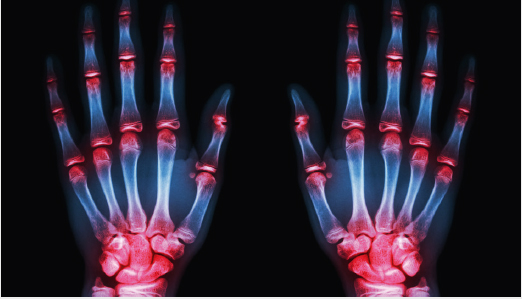

Inflammatory Arthritis such as Rheumatoid and Psoriatic arthritis, as well as osteoarthritis, can damage the multiple joints of the hand and wrist as well as the surrounding structures. They can cause damage to the articular surface of the joint. “Locking” of the joints can occur if fragments of bone break off the elbow and become lodged between the moving parts of the joint, causing reduced movement and pain. Synovitis or inflammation of the lining of the joints is seen with both conditions. Arthroscopic or key-hole surgery can wash out the wrist joint and allow your surgeon to remove loose pieces of bone or cartilage with small instruments. Synovitis of the lining of the wrist joint can be shaved away to give pain relief. Wrist, thumb base and finger joint replacement or fusion is recommended for patients with pain who have failed to respond to other treatments. This choice of treatment is tailored to each individual patient and need detailed discussion with your surgeon.